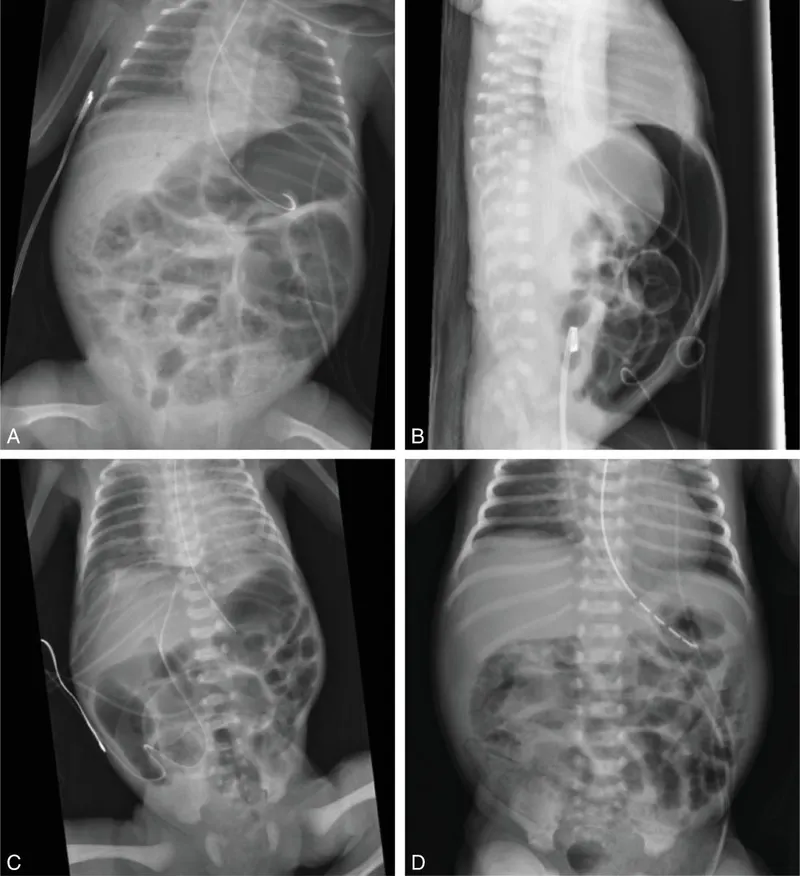

Imaging & Staging - X-Ray Clues

Abdominal X-ray is the primary imaging modality for diagnosis and staging, based on Modified Bell's criteria.

| II | Proven NEC | Pneumatosis intestinalis (hallmark); portal venous gas. > ⭐ Pneumatosis intestinalis (gas in the bowel wall) is the pathognomonic radiological sign for NEC. |

| III | Advanced NEC | Pneumoperitoneum (indicates perforation). |

- Pneumoperitoneum is a surgical emergency.

⭐ Pneumoperitoneum on an abdominal X-ray is an absolute indication for immediate surgical intervention.

- Pneumatosis intestinalis (gas in the bowel wall) is the pathognomonic sign on abdominal X-ray.

- Pneumoperitoneum indicates bowel perforation, an absolute indication for surgery.